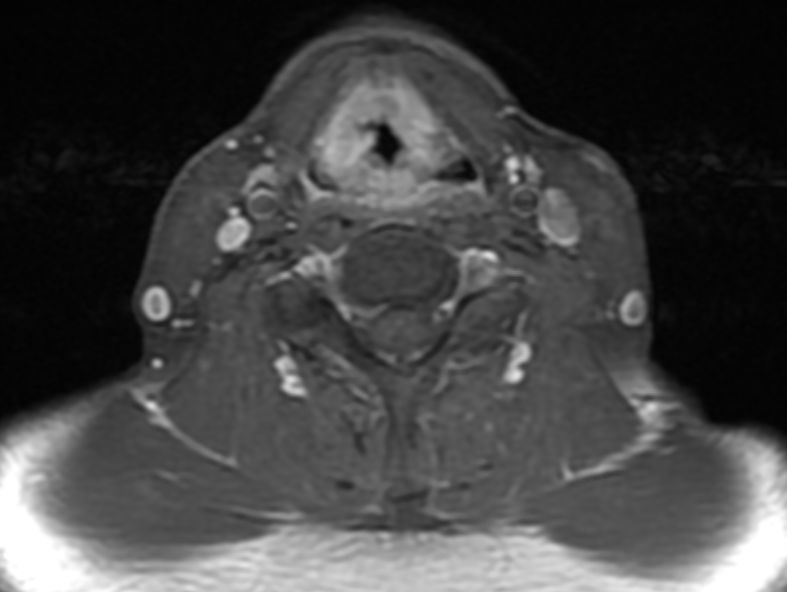

MRT: supraglottisch T3 No |

57-jähriger Mann mit langjährigem Alkohol- und Nikotinabusus. Seit 6 Monaten Schluckbeschwerden. Jetzt zunehmende Kachexie. MRT: Ausgedehntes supraglottisches Larynxkarzinom mit Schildkrorpel-Infiltration. Kehlkopfteilresektion mit ND. Histologie: unverhornendes Plattenepithelkarzinom, V0 R1 G1 - 2 Stadium post OP: pT3 pN0 (0/7) M0 | ||